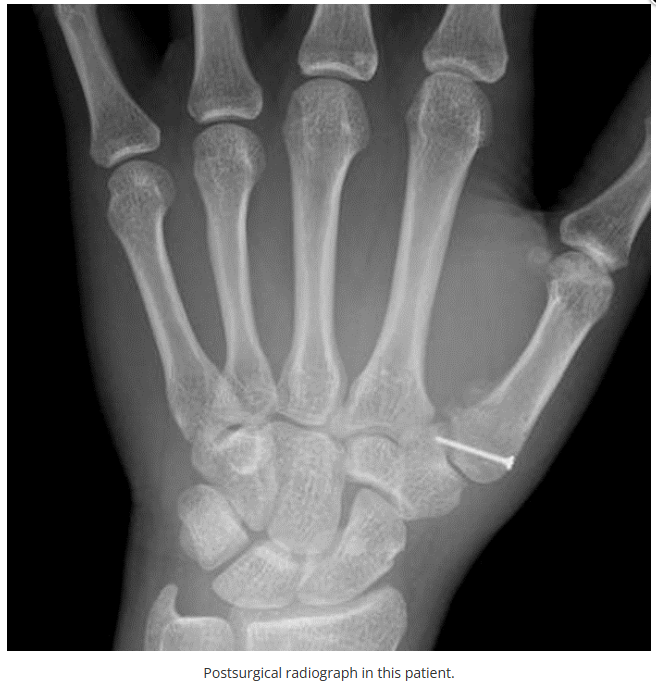

今天是腕部与手的X线片。所有X线片都

带有标注和说明

,可以选择长按图片,

自动翻译相关说明

。

进阶篇